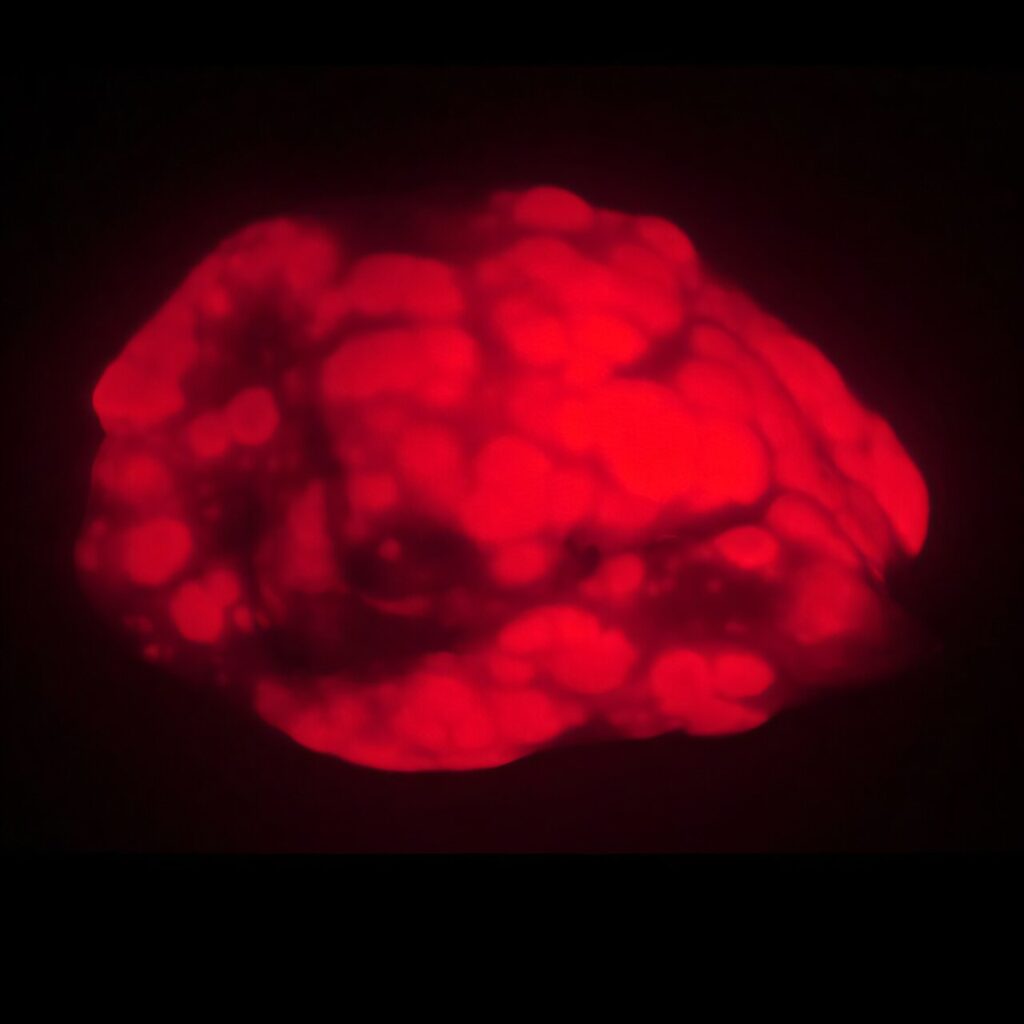

Les chercheurs suggèrent que certaines des modifications provoquées par ce désordre moléculaire pourraient potentiellement freiner l’évolution des mutations oncogènes vers des tumeurs. Pour explorer l’hypothèse, Shuldiner et ses collègues ont modifié génétiquement des souris pour développer des tumeurs pulmonaires marquées par fluorescence lorsqu’elles sont traitées avec des gènes administrés par inhalation.

Dans un modèle de cancer, les souris âgées développent des tumeurs pulmonaires moins nombreuses et plus petites (en rouge) que les animaux plus jeunes. © Emily Shuldiner

Les cancers ont été induits chez de jeunes souris (de quatre à 6 mois) et des souris âgées (20 à 21 mois). Chez les souris âgées, l’induction du cancer n’a été réalisée qu’une fois qu’elles avaient dépassé deux ans, afin de s’assurer qu’elles étaient réellement très âgées. Les taux de formation des tumeurs ont été mesurés 15 semaines plus tard en quantifiant les cellules cancéreuses au niveau de leurs poumons à l’aide de l’imagerie par fluorescence.

Les résultats ont révélé que le taux de cancer chez les jeunes souris était près de trois fois supérieur à celui des souris âgées. Les tumeurs étaient également plus volumineuses et donc plus agressives. « À tous les égards, les animaux les plus jeunes présentaient des cancers plus graves », affirme Shuldiner. Ces observations s’accordent avec des travaux antérieurs montrant une incidence plus faible du cancer chez les personnes très âgées.